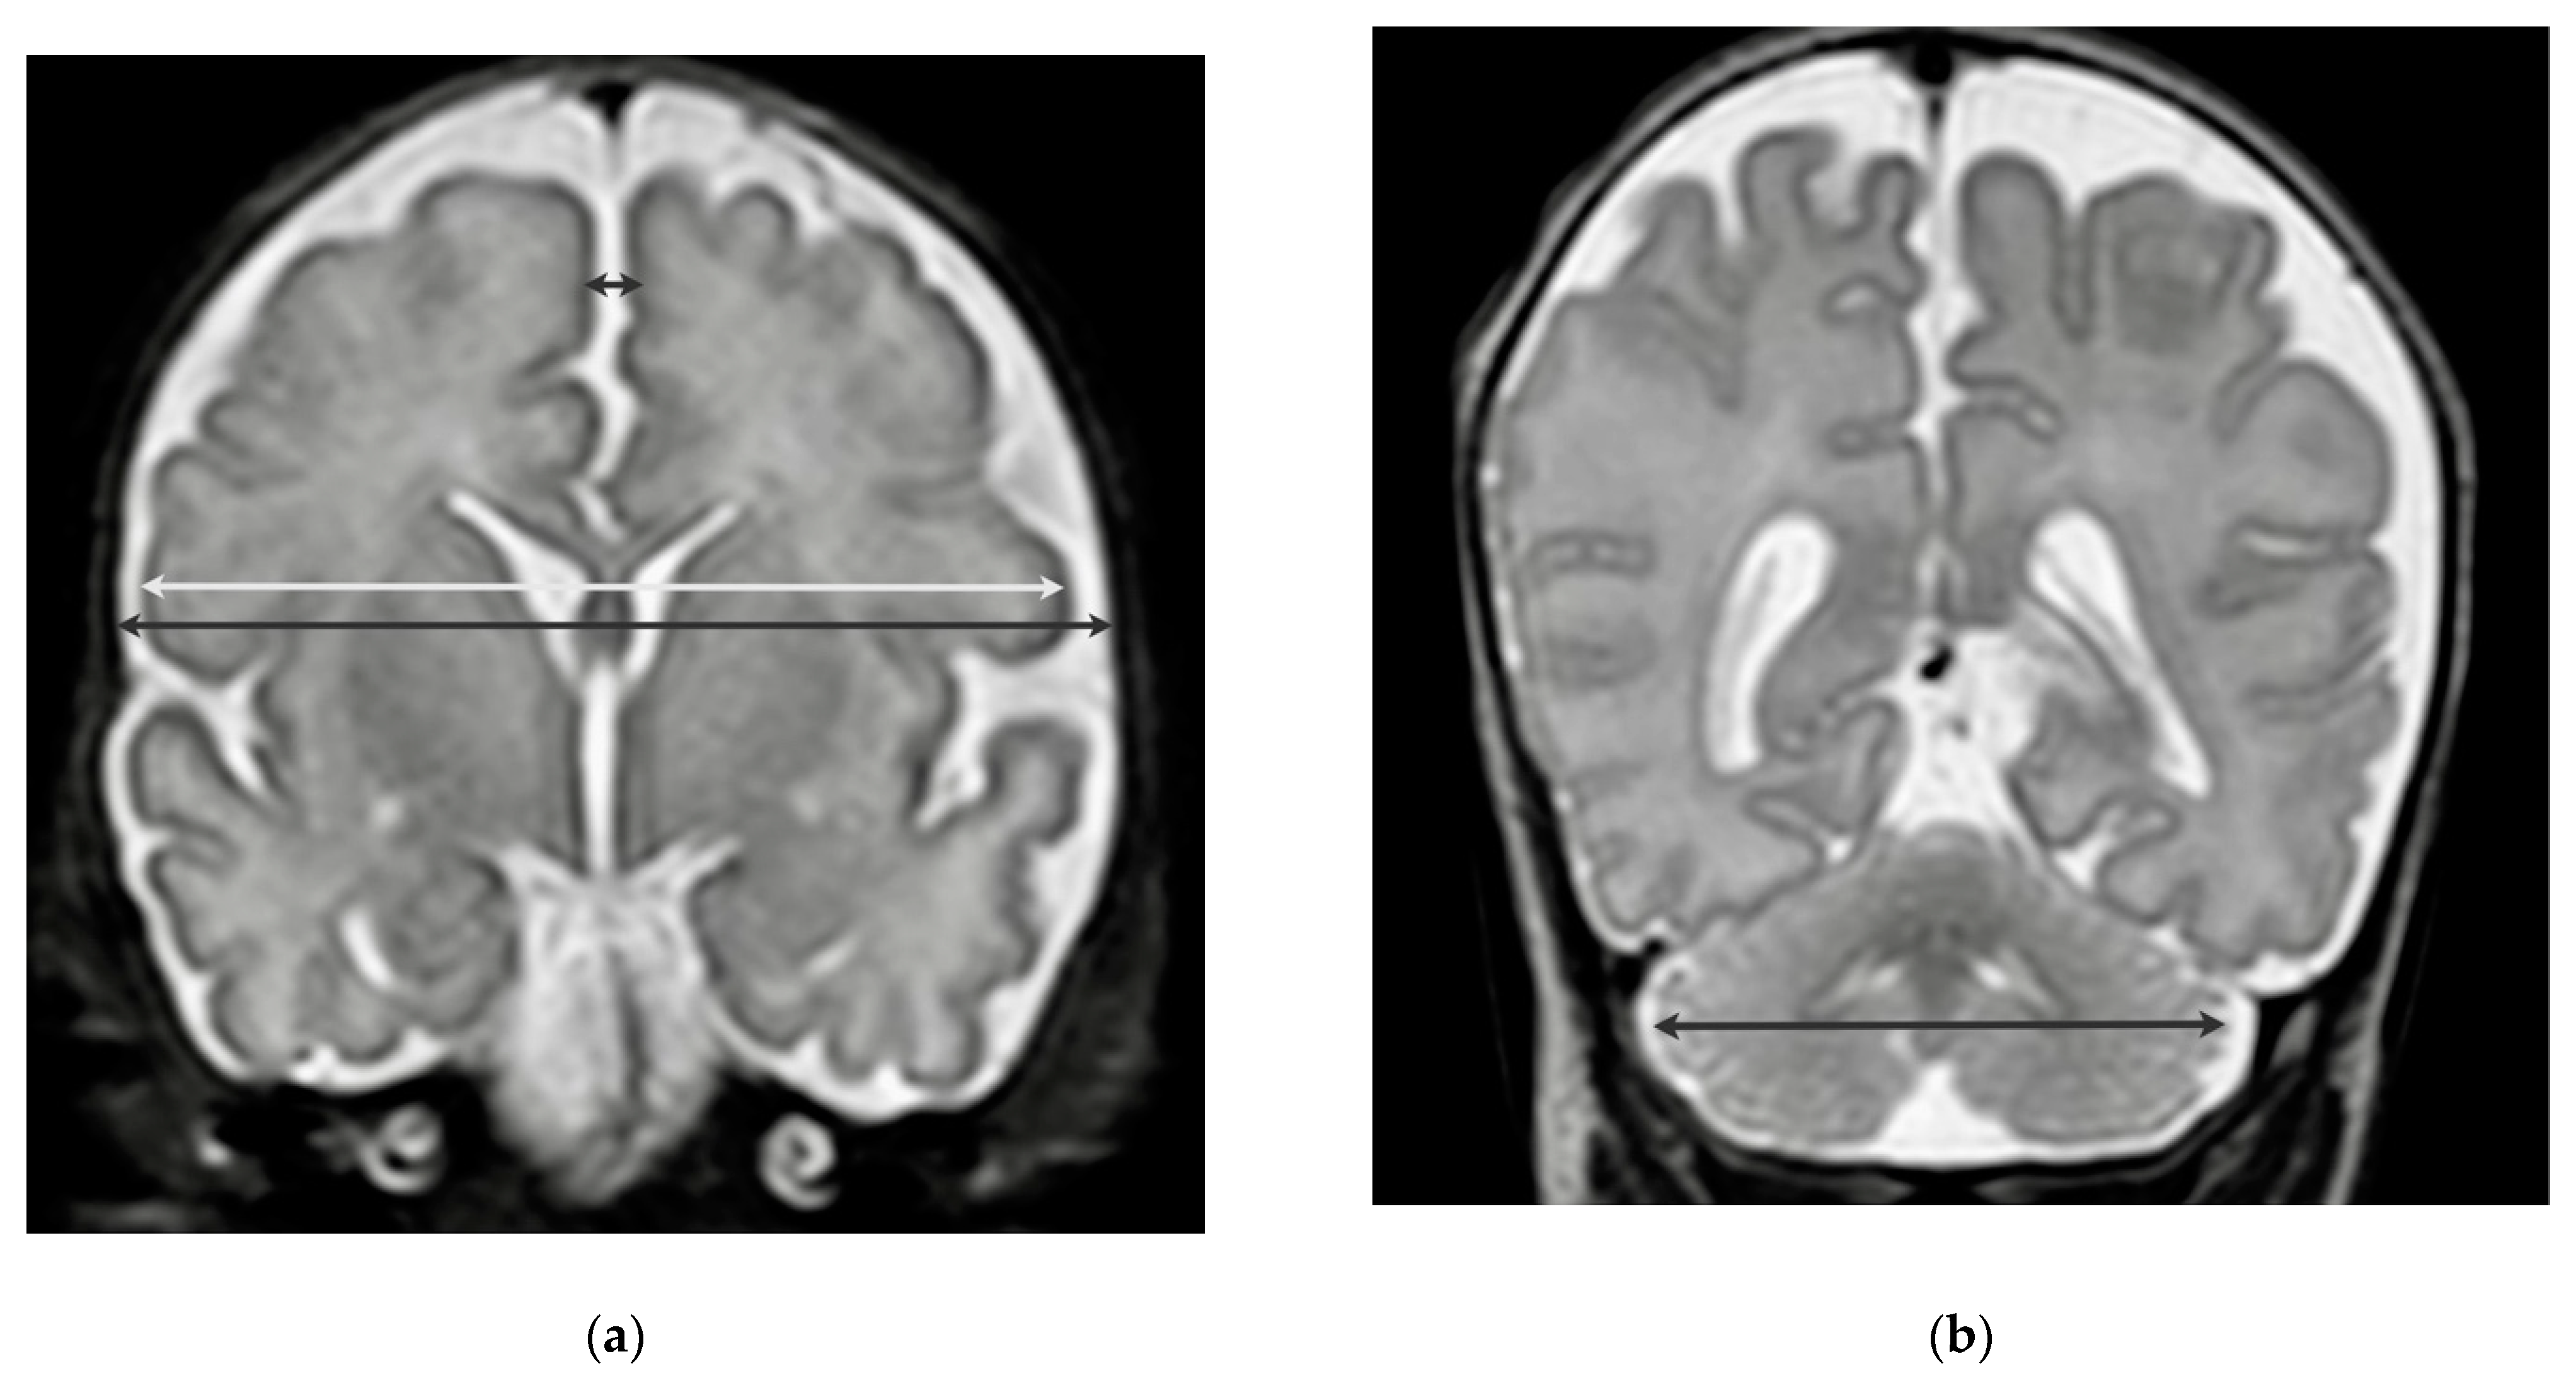

| cBPD, mm | 71.1 (68.9, 74.1) |

| bBPD, mm | 76.2 (73.7, 79.5) |

| IHD, mm | 2.5 (2.0, 3.0) |

| tCD, mm | 47.6 (45.7, 49.4) |

| cBPD, Z-Score | −2.3 (−2.8, −1.8) |

| bBPD, Z-Score | −2.2 (−2.9, −1.7) |

| IHD, Z-Score | 0,3 (−0.3, 0.8) |

| tCD, Z-Score | −0.7 (−2.1, 0.0) |